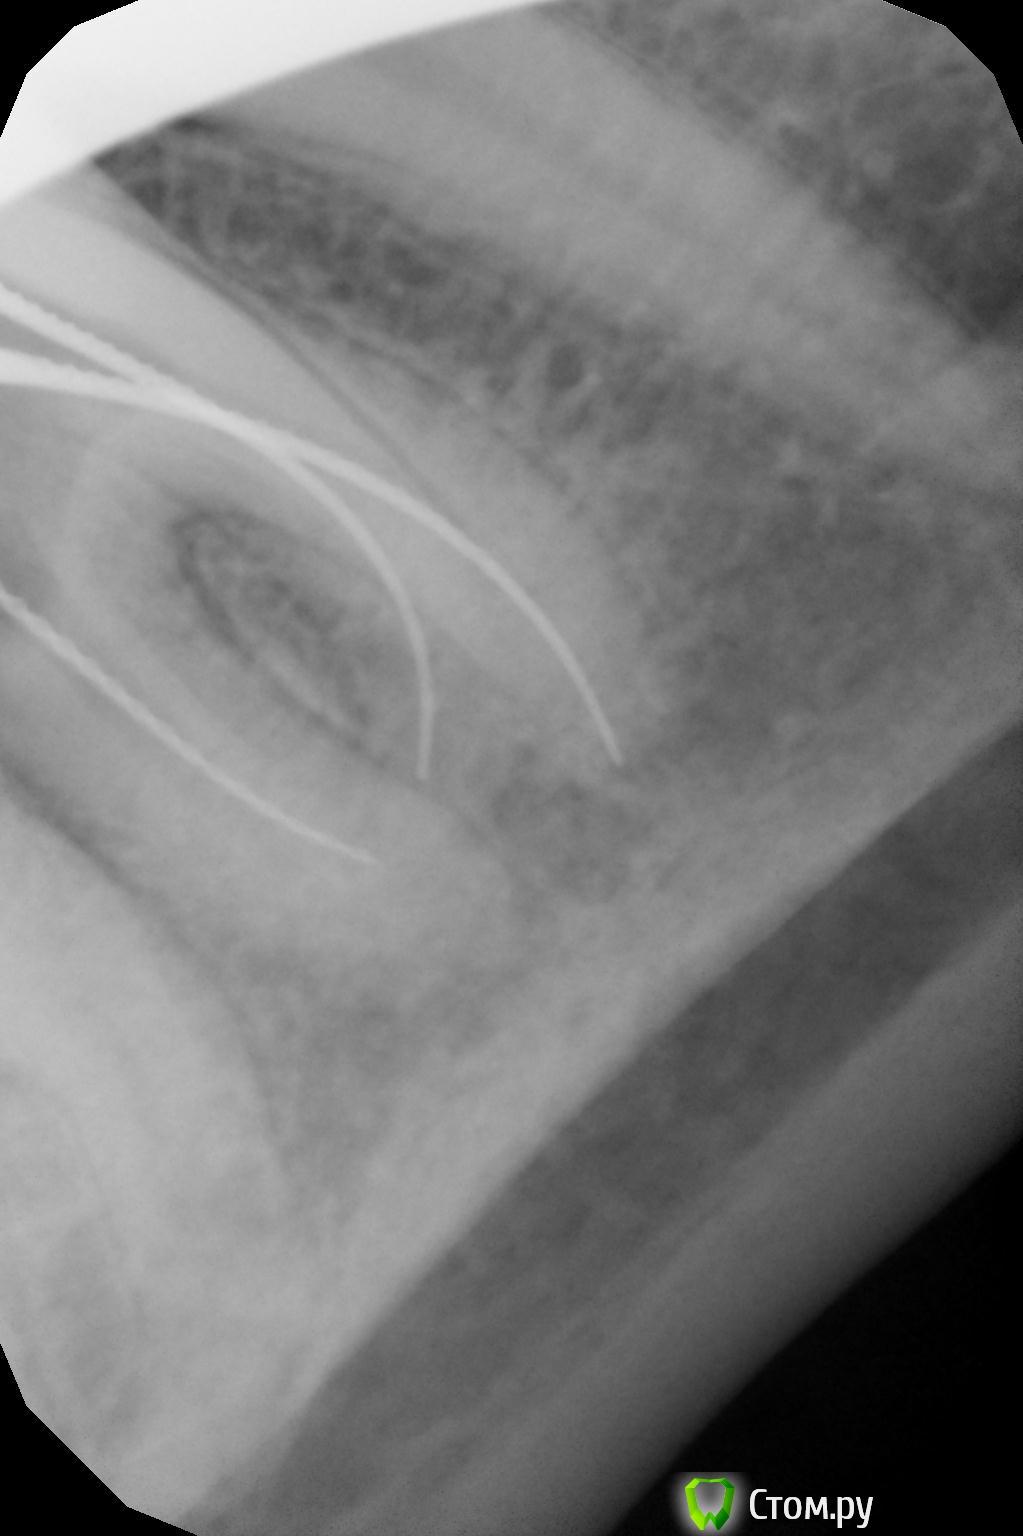

Girl Опубликовано 25 сентября, 2014 Поделиться Опубликовано 25 сентября, 2014 Сегодня шестерку лечила. Не очень поняла снимки По поводу дистального канала - если верить апексу, то я от апекса 0,5 мм. Пересняла отдельно дистальный канал с инструментом на размер меньше, тоже руководствуясь апекс-локатором, и все равно на снимке не дохожу. Почему так? Канал латерально открывается? И вообще, есть ощущения третьего корня 1 Ссылка на комментарий

Shaid Опубликовано 26 сентября, 2014 Поделиться Опубликовано 26 сентября, 2014 Т.е. аплок не показывал значение "за апексом"? Файл дальше тоже не идет? Ссылка на комментарий

Girl Опубликовано 26 сентября, 2014 Поделиться Опубликовано 26 сентября, 2014 (изменено) Аплок показывао, что я у самого апекса.Канал достаочно широкий, и за апекс тоже можно выйти. Я обычно 0, 5 мм не довожу, делаю снимок и пломбирую? А на этом снимке не вижу, что я до конца прошла...Вы думаете, я промахнулась и перфанула корень? Зуб 46, забыла сказать. Изменено 26 сентября, 2014 пользователем Girl Ссылка на комментарий

kitikf Опубликовано 26 сентября, 2014 Поделиться Опубликовано 26 сентября, 2014 Может быть 2 дистальных , причём начинается одним широким , а потом идёт раздвоение . В одно вы как раз попадаете. Ссылка на комментарий